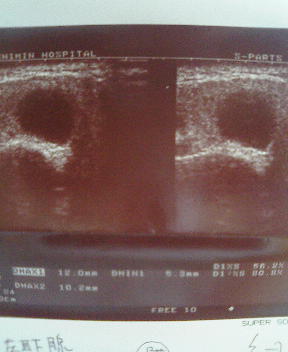

エコー像:

左耳下腺を たてに 切った画像です。

耳下腺 たて切り画像

よこに 切った画像です。

よこ切りエコー画像

計測すると、たて、横、深さが 14.3×12.0×10.2mm

先月計ったときは、たて×深さが12.5×8.5mm(よこ切りを測り忘れたので・・)

だったので、一ヶ月たたない間に全体的に2mm弱は大きくなってる様子。

エコーをとってもらった技師さんにみてもらったら、リンパ節だろうということだったし、他にも左腋下リンパ節や両側の顎下リンパ節、頚部のリンパ節も腫れているので、これもリンパ節だろう。なにかウイルス感染してリンパ節が腫れたんだろう・・・と。

すると、エコーの写真をみて先生は、

「耳下腺の真上にあるもんね、これは 耳下腺腫瘍 よ。腺腫かな~でも、耳下腺腫瘍で全身のリンパ節が腫れることはないから、もしかしたら 悪性リンパ腫 の可能性もある。2次感染を起こしてるはずだからまずフロモックス(抗生物質)を飲んで大きさに変化がなかったら、CTやMRIを撮って精密検査も考えようね」